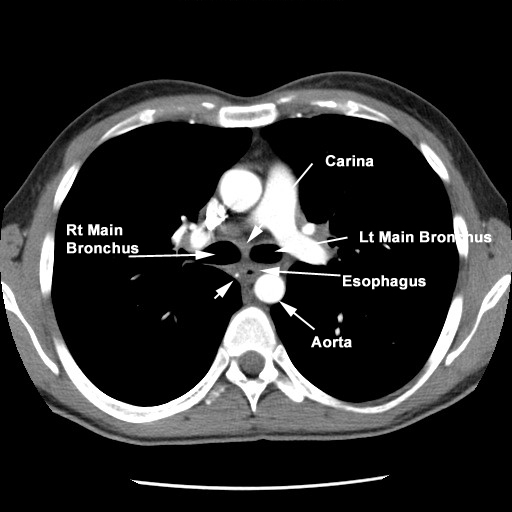

- The thoracic portion Superior

Mediastinum Superior

Mediastinum At Carina At

- Anterior

- Trachea

- Left main stem bronchus

- Pericardium

- behind and to the right of aortic

arch

- Posterior

- Vertebral column

- Hemiazygous vein

- right aortic intercostal arteries

- aorta near diaphragm

- Right

- right pleura

- azygous vein

- Left

- aortic arch

- left subclavian artery

- left pleura

- descending aorta